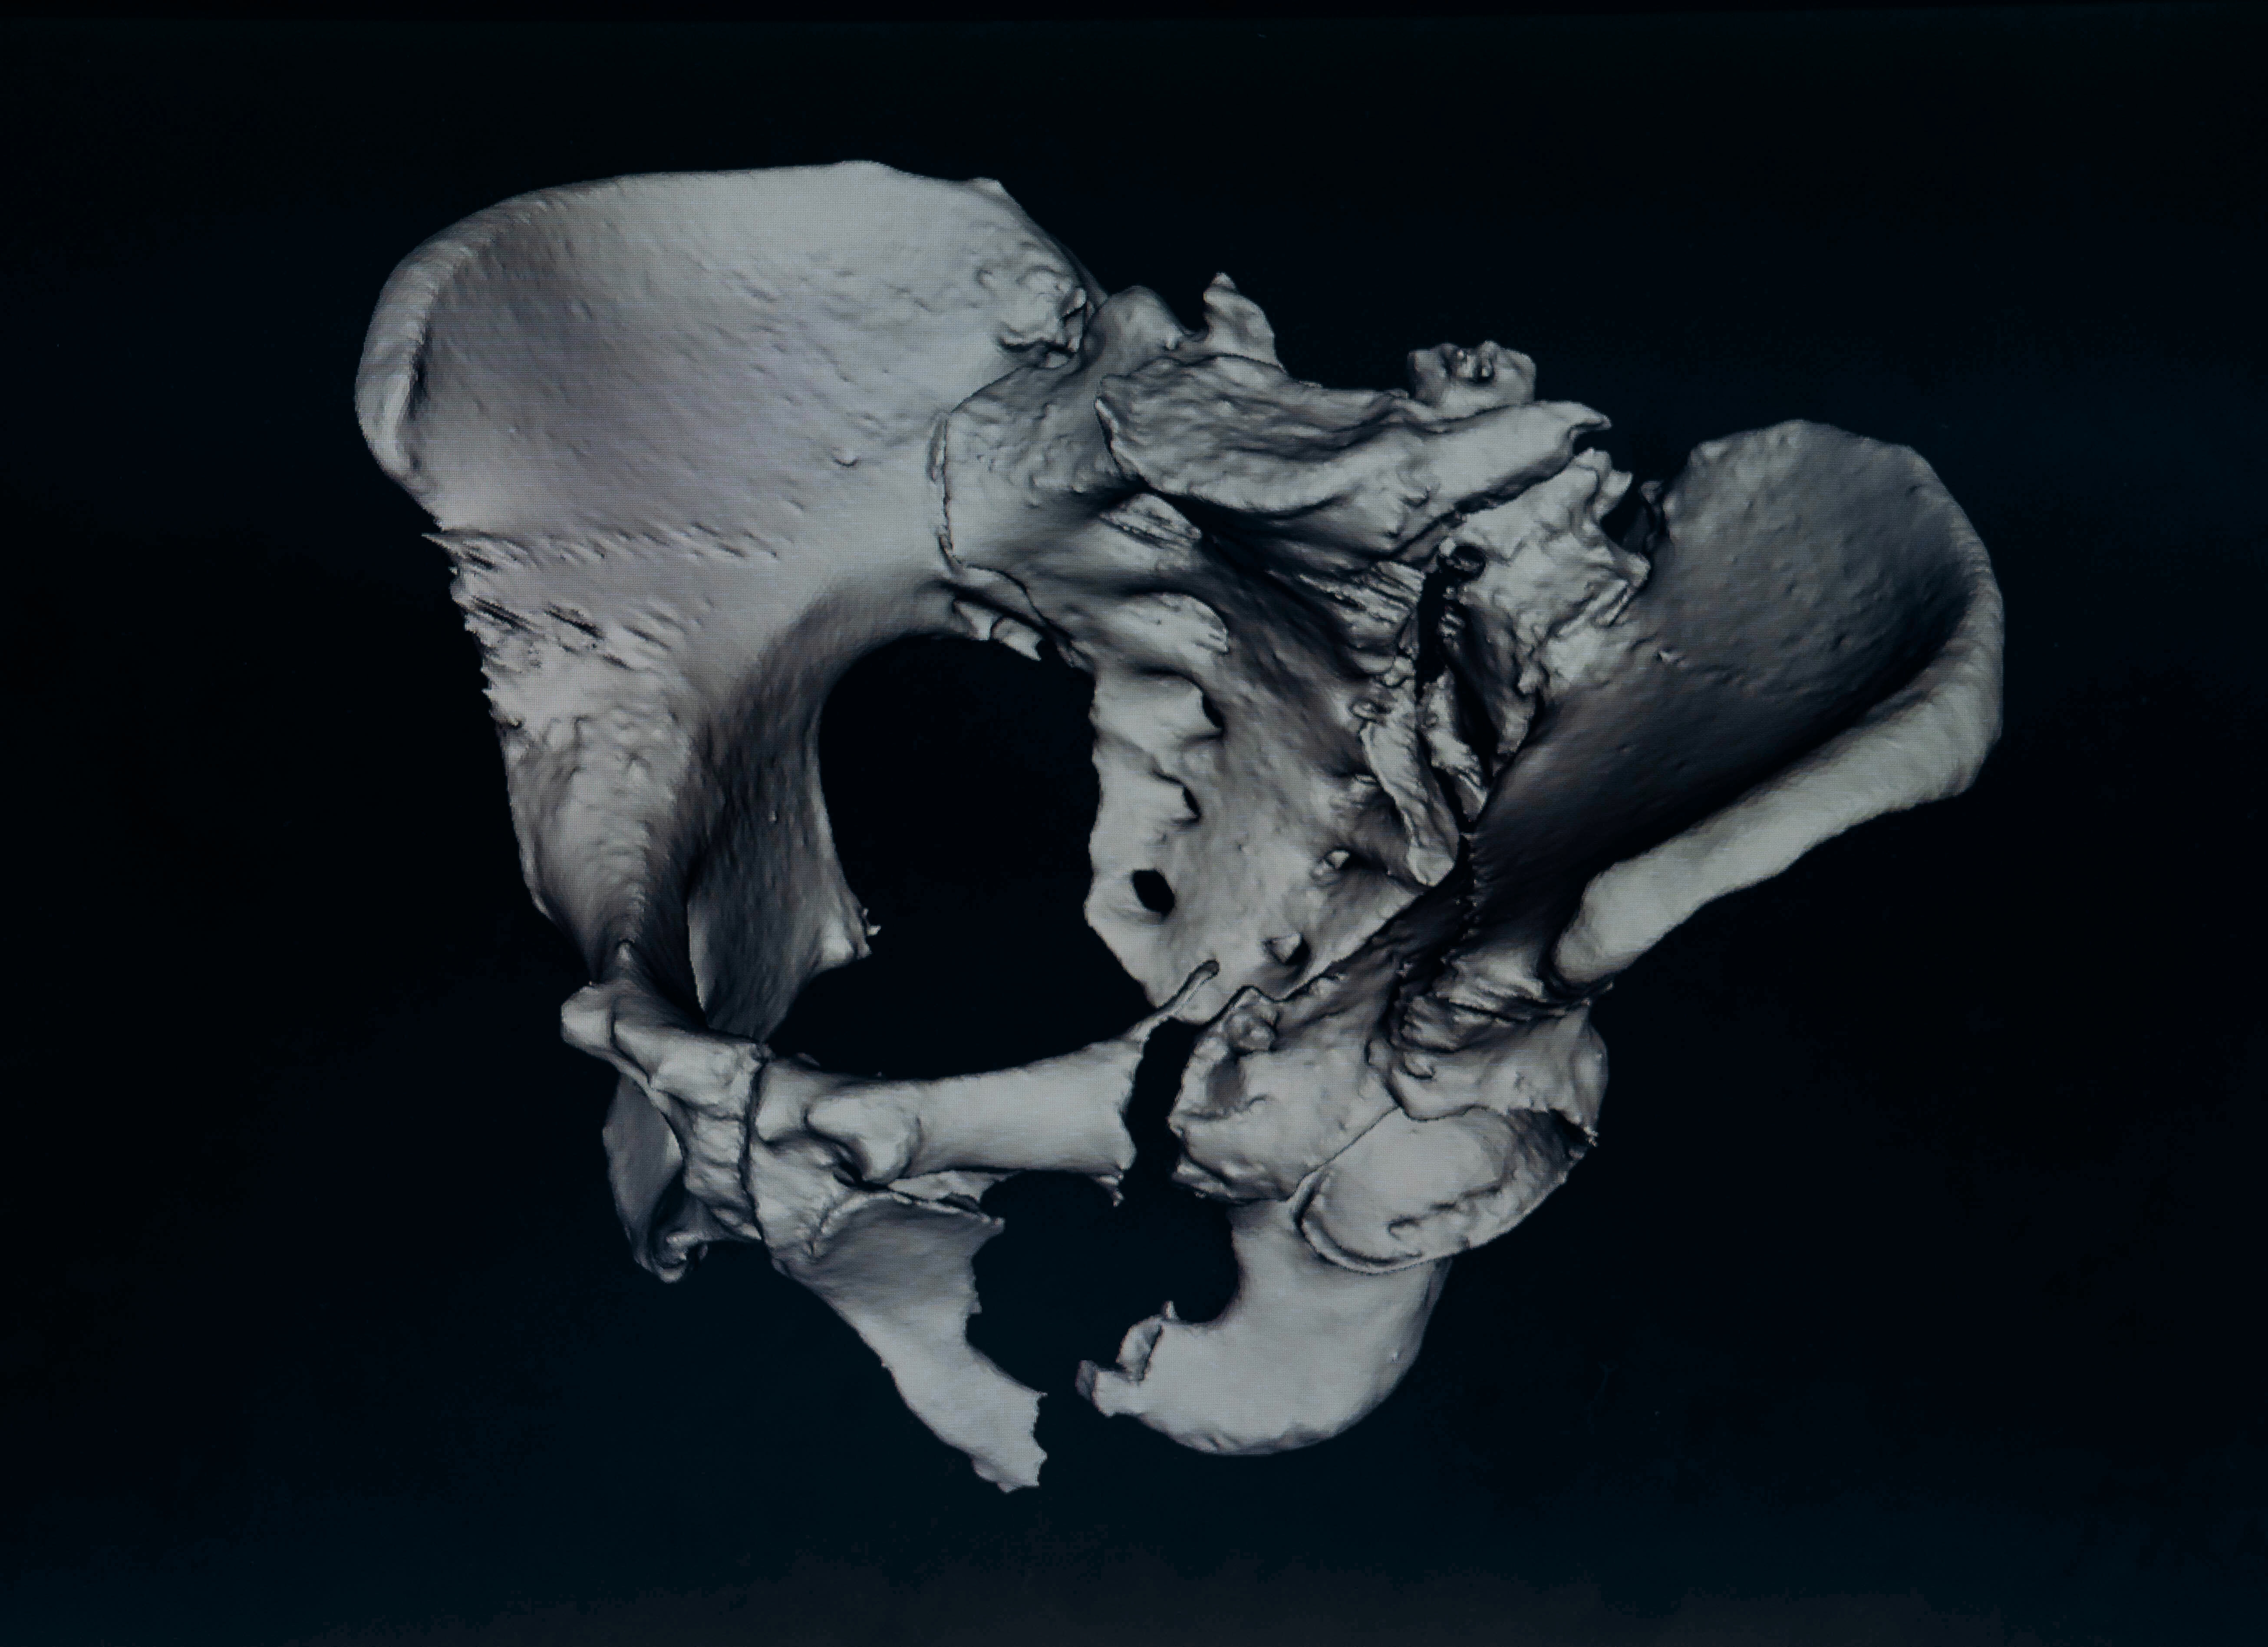

04 의료용 3D 모델링 Medical 3D Modeling & Visualization

가상 시뮬레이션 및 학술 연구용 콘텐츠 개발에 최적화된 고정밀 해부학 3D 모델링 솔루션을 제공합니다.

고정밀 해부학 구조 구현 High-Fidelity Anatomical Modeling

의료 데이터를 직접 해석(Segmentation)하여, 자동화 도구가 놓치기 쉬운 미세한 인체 구조까지 정교하게 추출합니다.